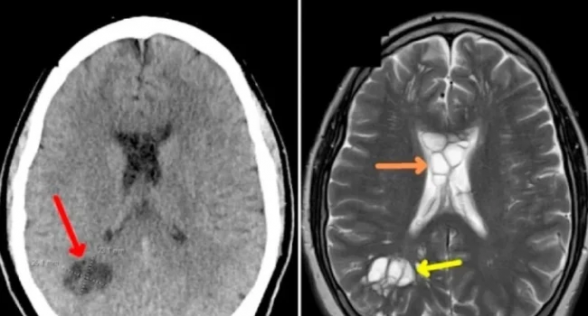

Սկզբում բժիշկները կասկածում էին, որ տղամարդը միգրեն ունի, բայց համակարգչային տոմոգրաֆիան ցույց է տվել, որ տղամարդու ուղեղը լիքն է մակաբույծներով. խոզի երիզորդի թրթուրները կիստա էին առաջացրել ուղեղի երկու կողմերում, գրել է Bild-ը։

Այս արտասովոր երևույթի բժշկական անվանումն է նեյրոցիստիցերկոզ։ Այս հիվանդության ամենատարածված պատճառը թերի տապակած և եփված խոզի մսի չափից ավելի օգտագործումն է։